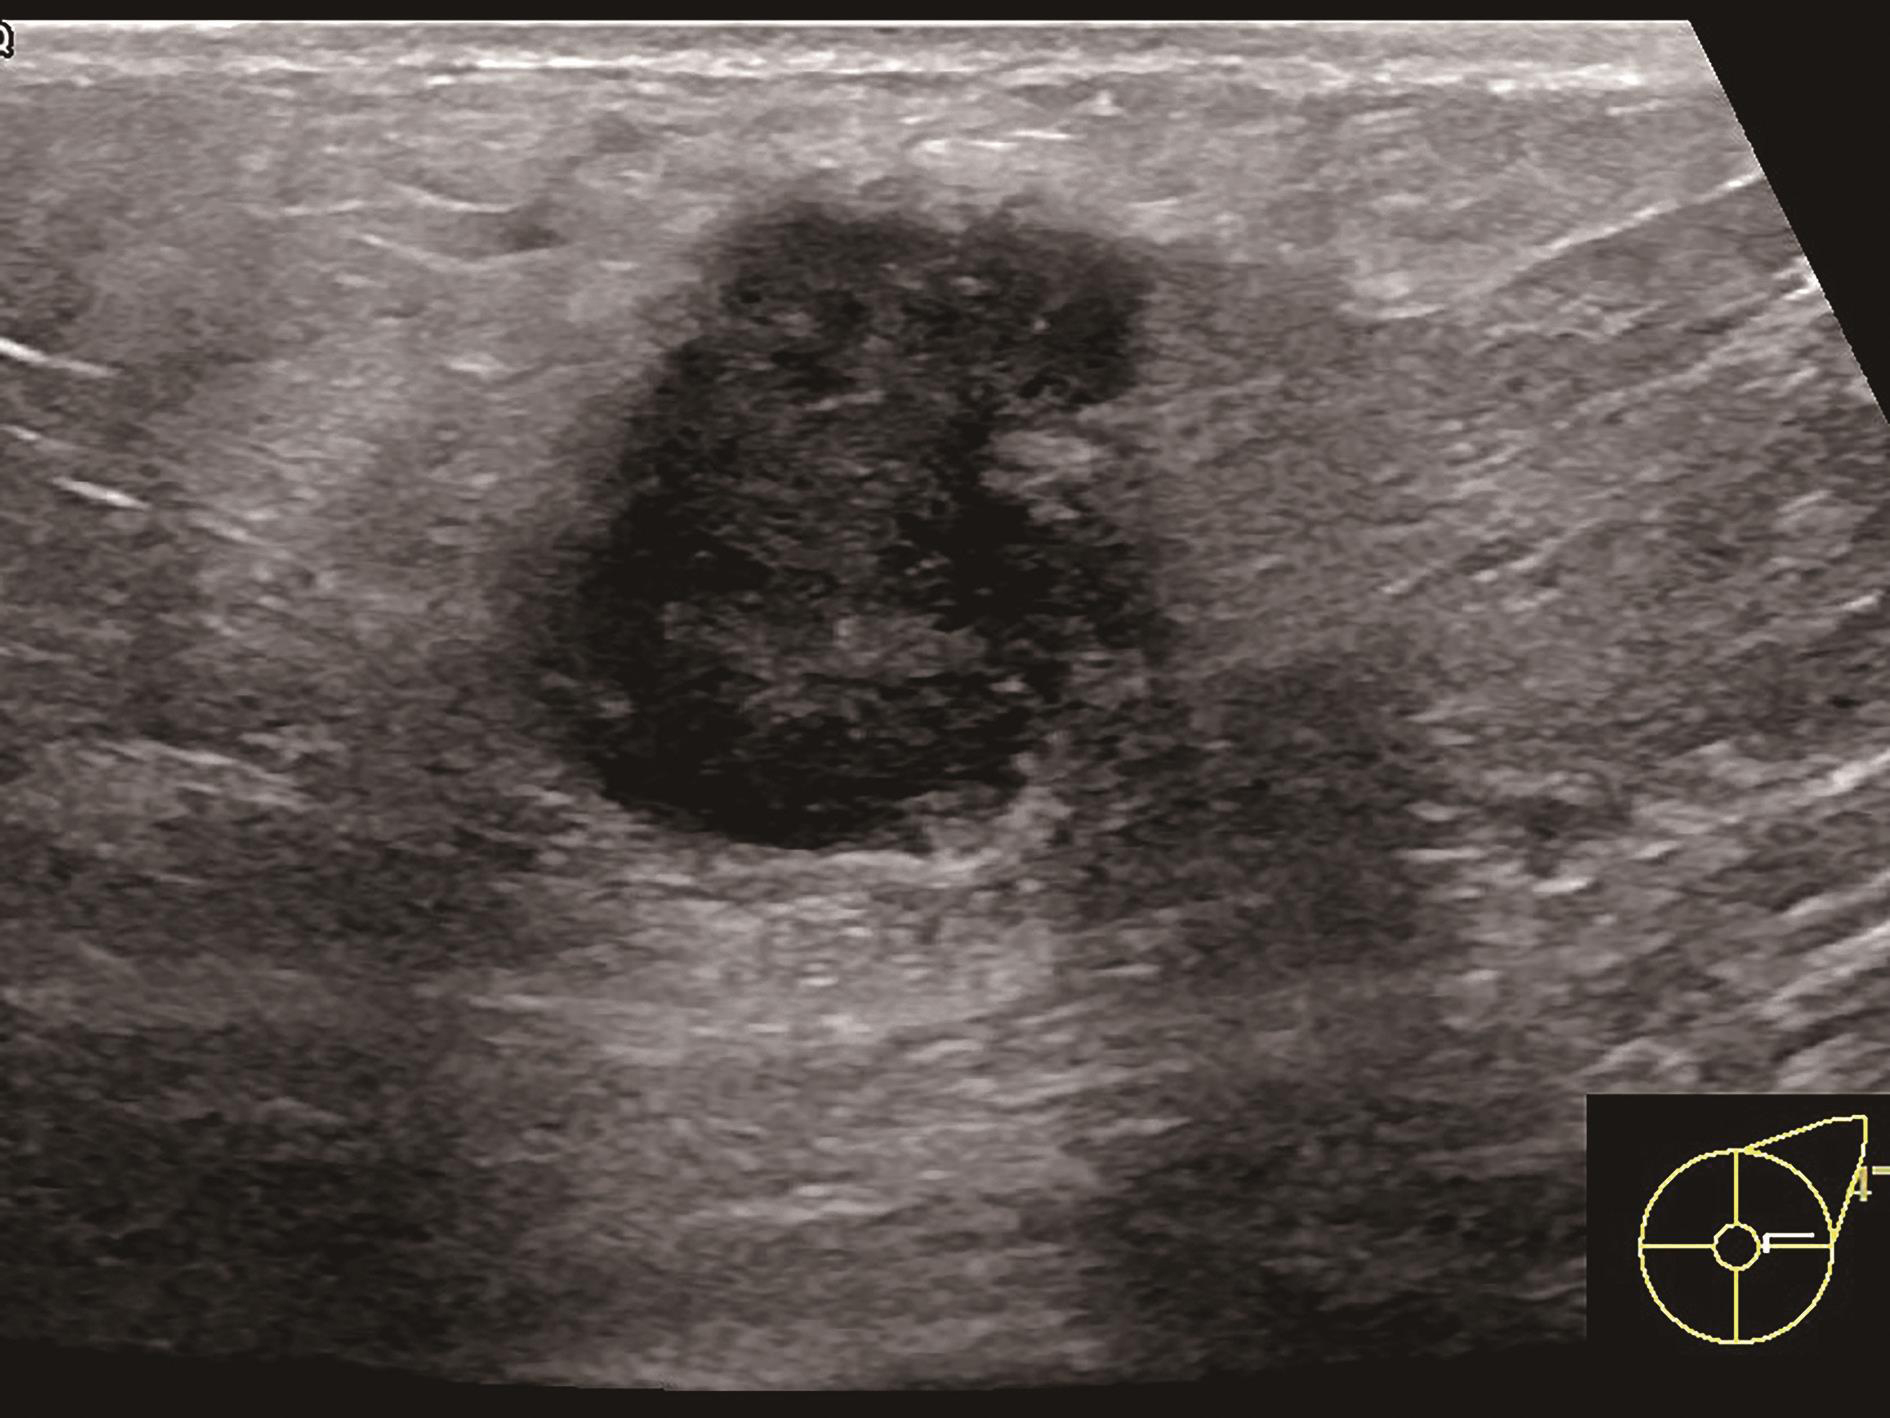

图2-2-3 病灶最大切面

图2-2-4 纵横比大于1或边界最不规整切面

图2-2-5 血流信号最丰富或有滋养血管切面